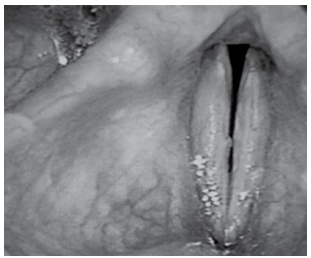

Avalie cuidadosamente, a seguir, a imagem de uma paciente de 41 anos com disfonia funcional.

(Mara Behlau, Voz: o livro do especialista)

A figura é compatível com uma fenda